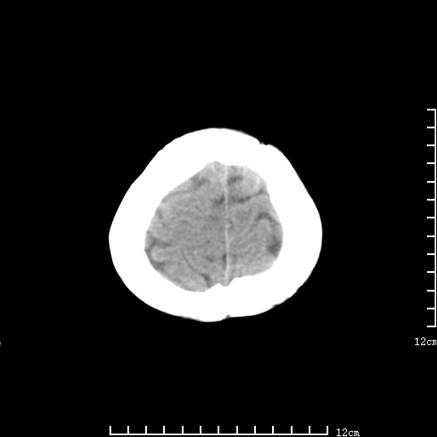

以下是引用jiajie在2008-9-5 22:25:00的发言:[br]男,22岁,头痛1月余。脑室、脑池内病变ct值约-120hu。[br][br]双侧侧脑室内低密度影充填,出现脑脊液脂肪平面,脑池内亦可见弥散分布的斑点状低密度影,脑室脑池未见明显扩大。[br]考虑胆脂瘤破裂后内容物进入脑脊液。